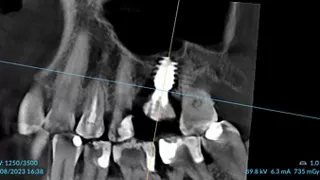

10a. 10b. 10c. 3D scans and radiograph control of the implantplacement.

10a

10b

10c